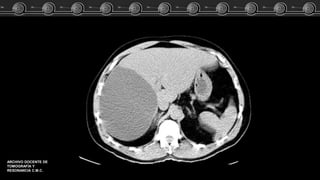

Adenoma, Hemangioma ó HNF?? Caso Clínico

Fem de 83 años…. El estudio TC demostró lesión focal a nivel del lóbulo

izquierdo del higado.